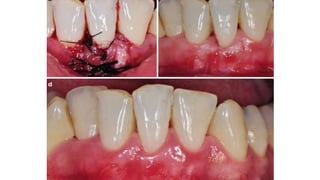

• #13 Class I gingival recessions– Baseline (a), recession depth of 3 mm (b), planning the papillary incisions (c), horizontal incisions performed as reported by Zucchelli and de Sanctis (d)

• #14 flap raised without releasing incisions (e), papillae de- epithelialization (f), flap coronally advanced and sutured as much as possible (with no tension) (g), 14-day follow-up (h), 4-month follow-up (i)